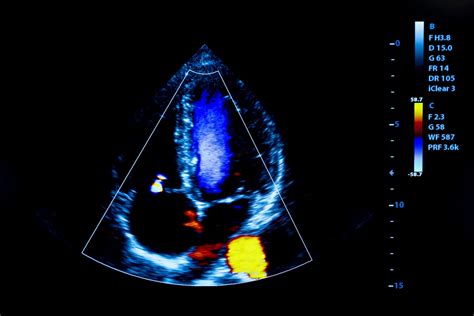

Nors prieinamų RUGA modelių pagaminama daugiau, o įvairių modelių išvaizda ir galimybės skiriasi, jie turi ir tam tikrų bendrų savybių. Jie susideda iš ekrano ir bendro arba specialiojo daviklio, kuris paprastai sukuria dvimatį pilkos spalvos vaizdą su mažesne erdvine ir laiko raiška nei aukštos klasės sistemos. Daugumoje sistemų yra spalvota doplerio vaizdavimo galimybė, turinti tam tikrų apribojimų. RUGA turi ribotą pagrindinių funkcijų valdymo galimybę - gylio ir stiprumo reguliavimas, vaizdo fiksavimas ir saugojimas. Turimi matavimai paprastai apsiriboja atstumo ir ploto vertinimais. Nors ankstesni aparatai leidžia saugoti duomenis tik bendrais vaizdų ar filmų formatais, kai kurie naujesni aparatai leidžia išsaugoti ir įrašyti vaizdus skaitmeninėje medicinos vaizdų bazėje (DICOM). Spektrinė doplerio funkcija šiuo metu nėra įdiegta nė į vieną RUGA modelį. Be to, daugelyje aparatų nėra M-mode galimybės ir tuo pat metu rašomos elektrokardiografijos funkcijos.

Spektrinio doplerio trūkumas neleidžia visapusiškai įvertinti vožtuvo ligos sunkumo ir sistolinio plaučių arterijos slėgio, tačiau galima nustatyti morfologines anomalijas ir netiesioginius ligos sunkumo požymius, atliekant kokybinę vožtuvo funkcijos analizę. Vožtuvo morfologija ir turbulentinio srauto buvimas ar nebuvimas yra požymiai, kuriuos galima aptikti RUGA ir kurie skatina tolesnį paciento ištyrimą.

Remiantis įvairių tyrimų duomenimis, RUGA galimybės diagnozuoti aortos, mitralinio ar triburio vožtuvų disfunkciją, palyginti su aukštos kokybės aparatų galimybėmis, svyruoja. Tokį skirtingų studijų rezultatų heterogeniškumą lemia tiriami vožtuvai ir dominuojančios ligos mechanizmai (stenozė ar nesandarumas).